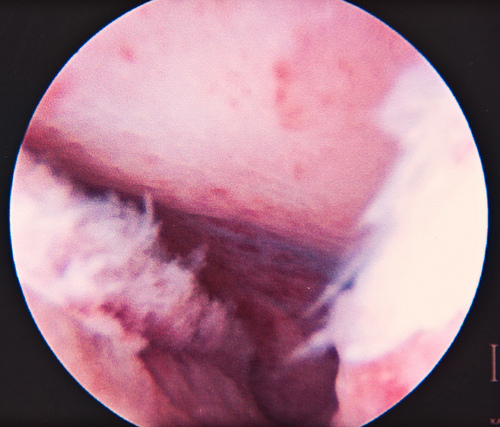

Left Fallopian Tube - Normal. Open & nothing wrong.

Right Fallopian Tube - Not normal. It was open so they didn't have to unblock it. But there was a lot of scar tissue, it was enlarged & very twisted. This increases my risks of ectopic pregnancy by a lot. Not sure if this means I skip IUI & head to IVF instead. But since it's not block they left it as is.

Ovaries - Normal. I'm assuming they are the blue/white things in the photos. My tubes are also blue in colour due to the dye they used.